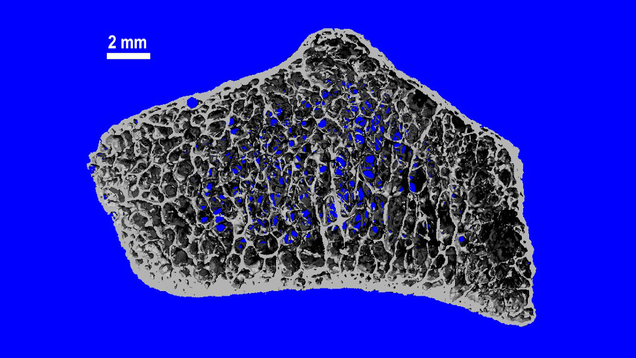

Long-term exposure to microgravity results in the loss of bone density, and new research reveals the disturbing extent to which this happens and finds that astronauts may never fully recover.

Source: Gizmodo – Astronauts Can Suffer a Decade of Bone Loss During Months in Space, New Research Suggests